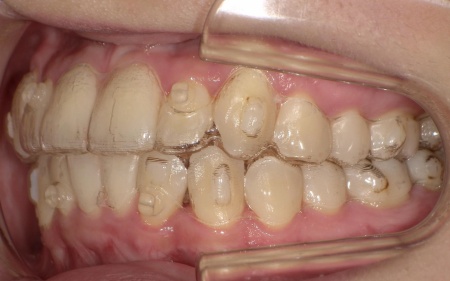

20代女性 八重歯と歯並びの乱れをマウスピース矯正装置で改善した症例

「上下の八重歯が気になる」とご相談いただきました。

拝見したところ、歯が正しく並ぶためのスペースが不足しており、歯が重なって生えてしまう叢生(そうせい)の状態が全体的に見られました。

特に上下の糸切り歯が外側にずれている、いわゆる八重歯が目立っています。